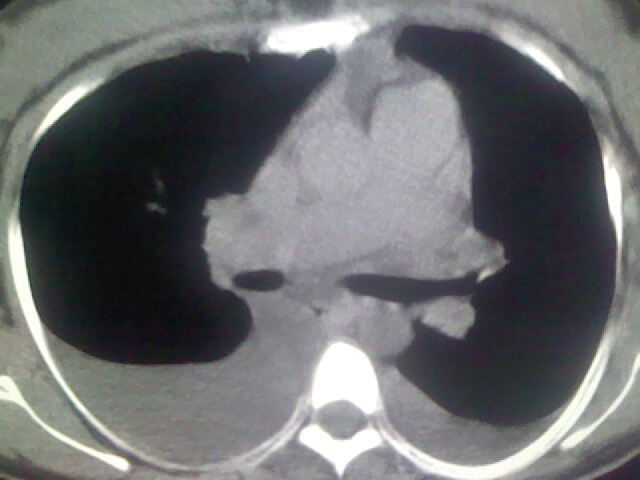

女,24,剖腹产后,突觉胸痛,干咳,不能平卧

胸水 感染 心影增大 肺水肿?

双肺“肺泡性肺水肿” “胸腔积液”!

双侧胸腔积液,肺泡性肺水肿。后纵隔好像有占位。

肝脾大,双侧胸腔积液,双肺水肿,肺动脉[包括远端小动脉],左右心房,左心室增宽,右心室主动脉无明显改变,符合左心功能不全征;;建议除外二尖瓣关闭不全,扩张性心肌病